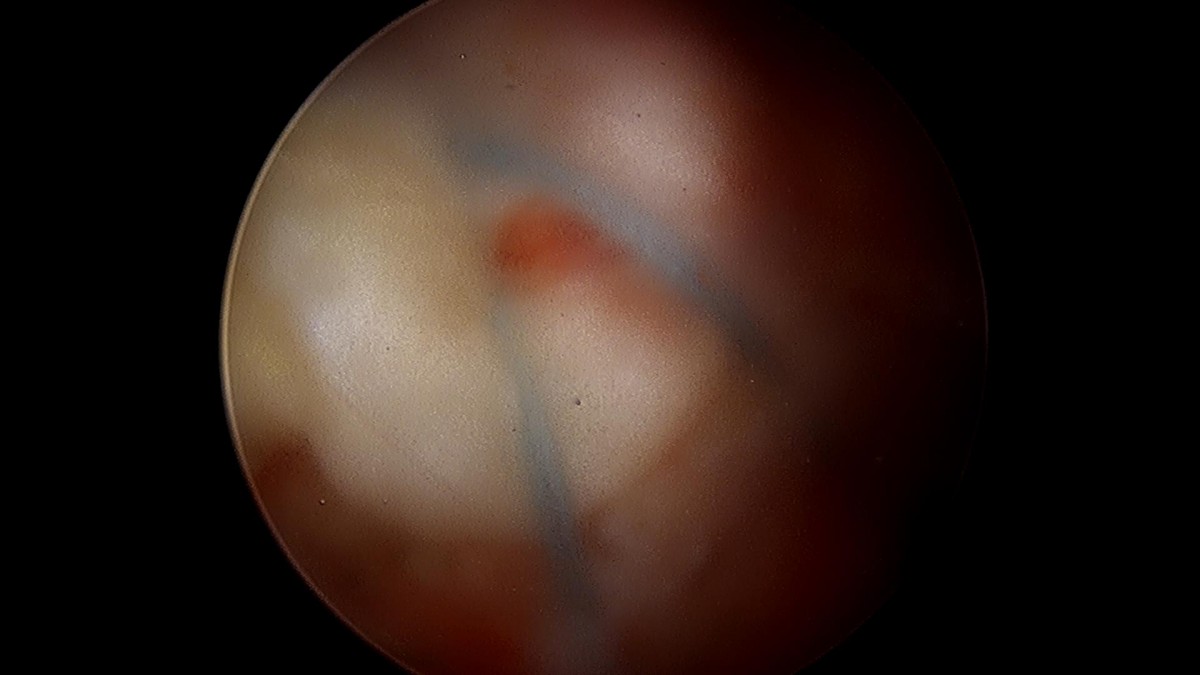

배우한원장님 어깨 회전근개 봉합술 (1599)제연O 환자

작성자 최고관리자 댓글 0건 조회 1,813회 작성일 22-02-23 15:13